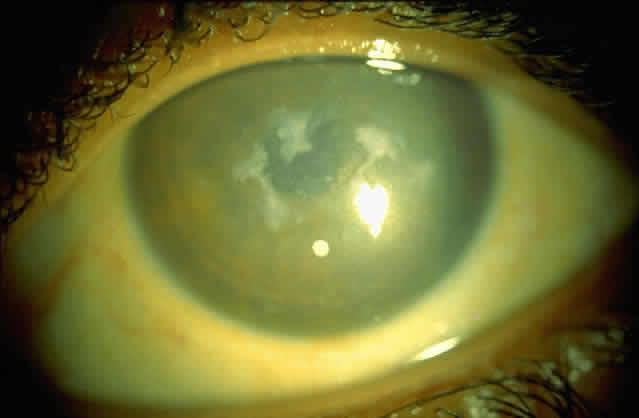

Bacterial corneal infections are caused by a wide variety of organisms. Pneumococcus seems to be the most common causative organism (Fig. 2); however, staphylococcal, pseudomonal, and gonococcal infections frequently are encountered.3 This may be related to chronic dacryocystitis.5